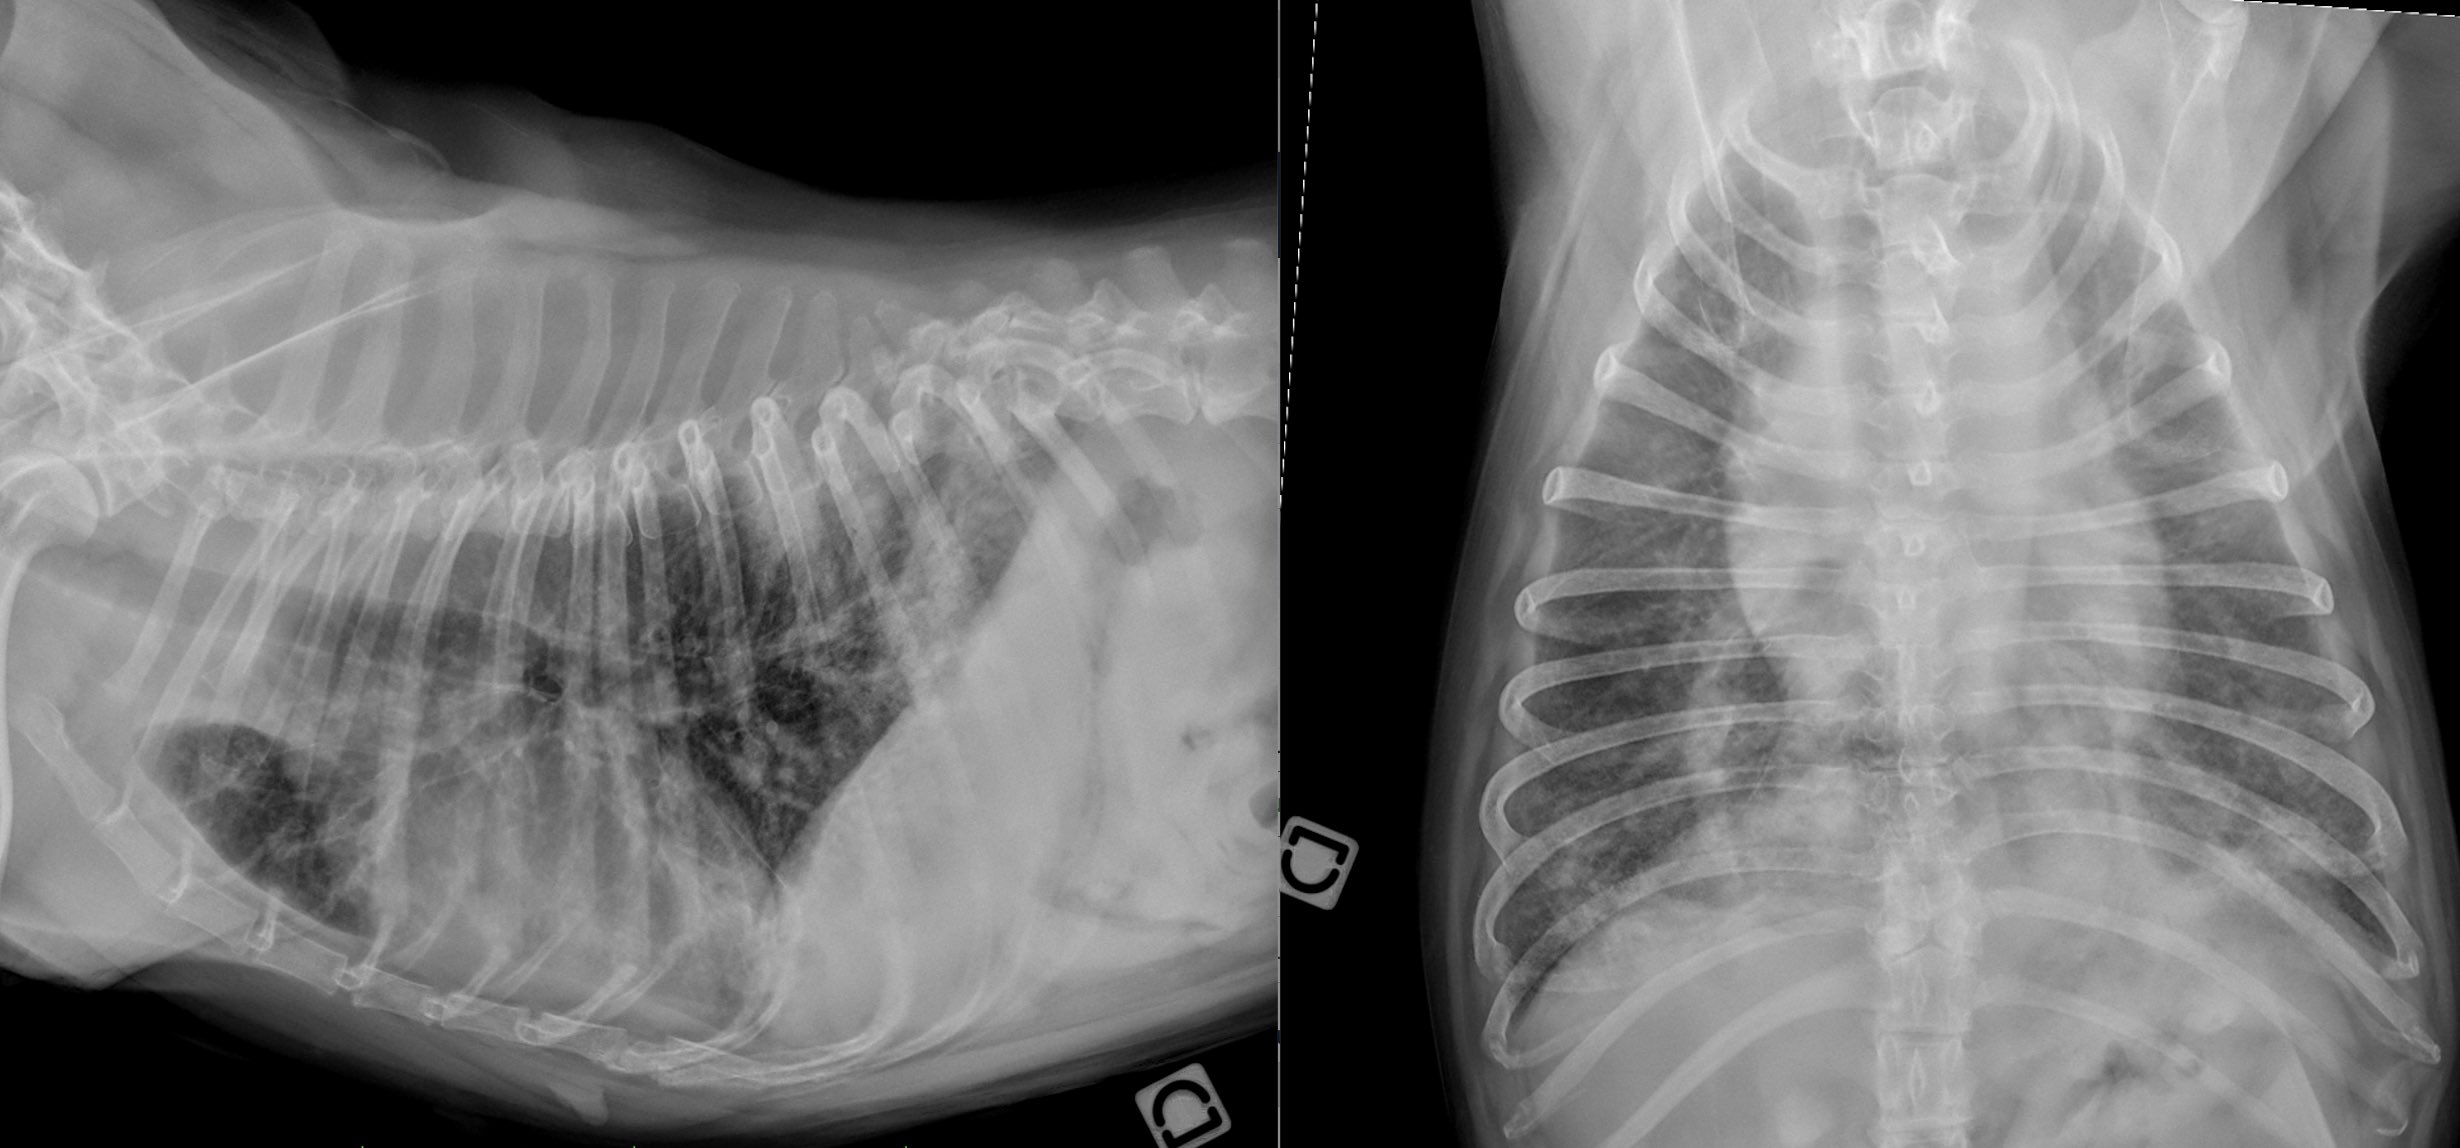

Reconnaître les types d’opacification pulmonaire

Quelles sont les opacités anormales visibles sur ces radiographies (profil latéral droit et VD) ? 1 – Opacité bronchique. 2 – Opacité interstitielle et bronchique. 3 – Opacité bronchique et alvéolaire. Si vous avez coché le choix 3, c’est la bonne réponse 😁 La méthode d’interprétation des anomalies du parenchyme pulmonaire… Lire la suite